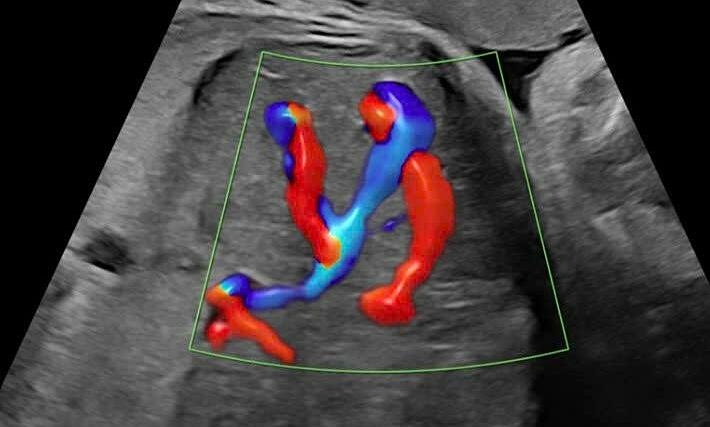

Êkíp phẫu thuật tiếp cận phần nhu mô phổi chứa tổn thương. Ảnh: Bệnh viện Đa khoa Tâm Anh